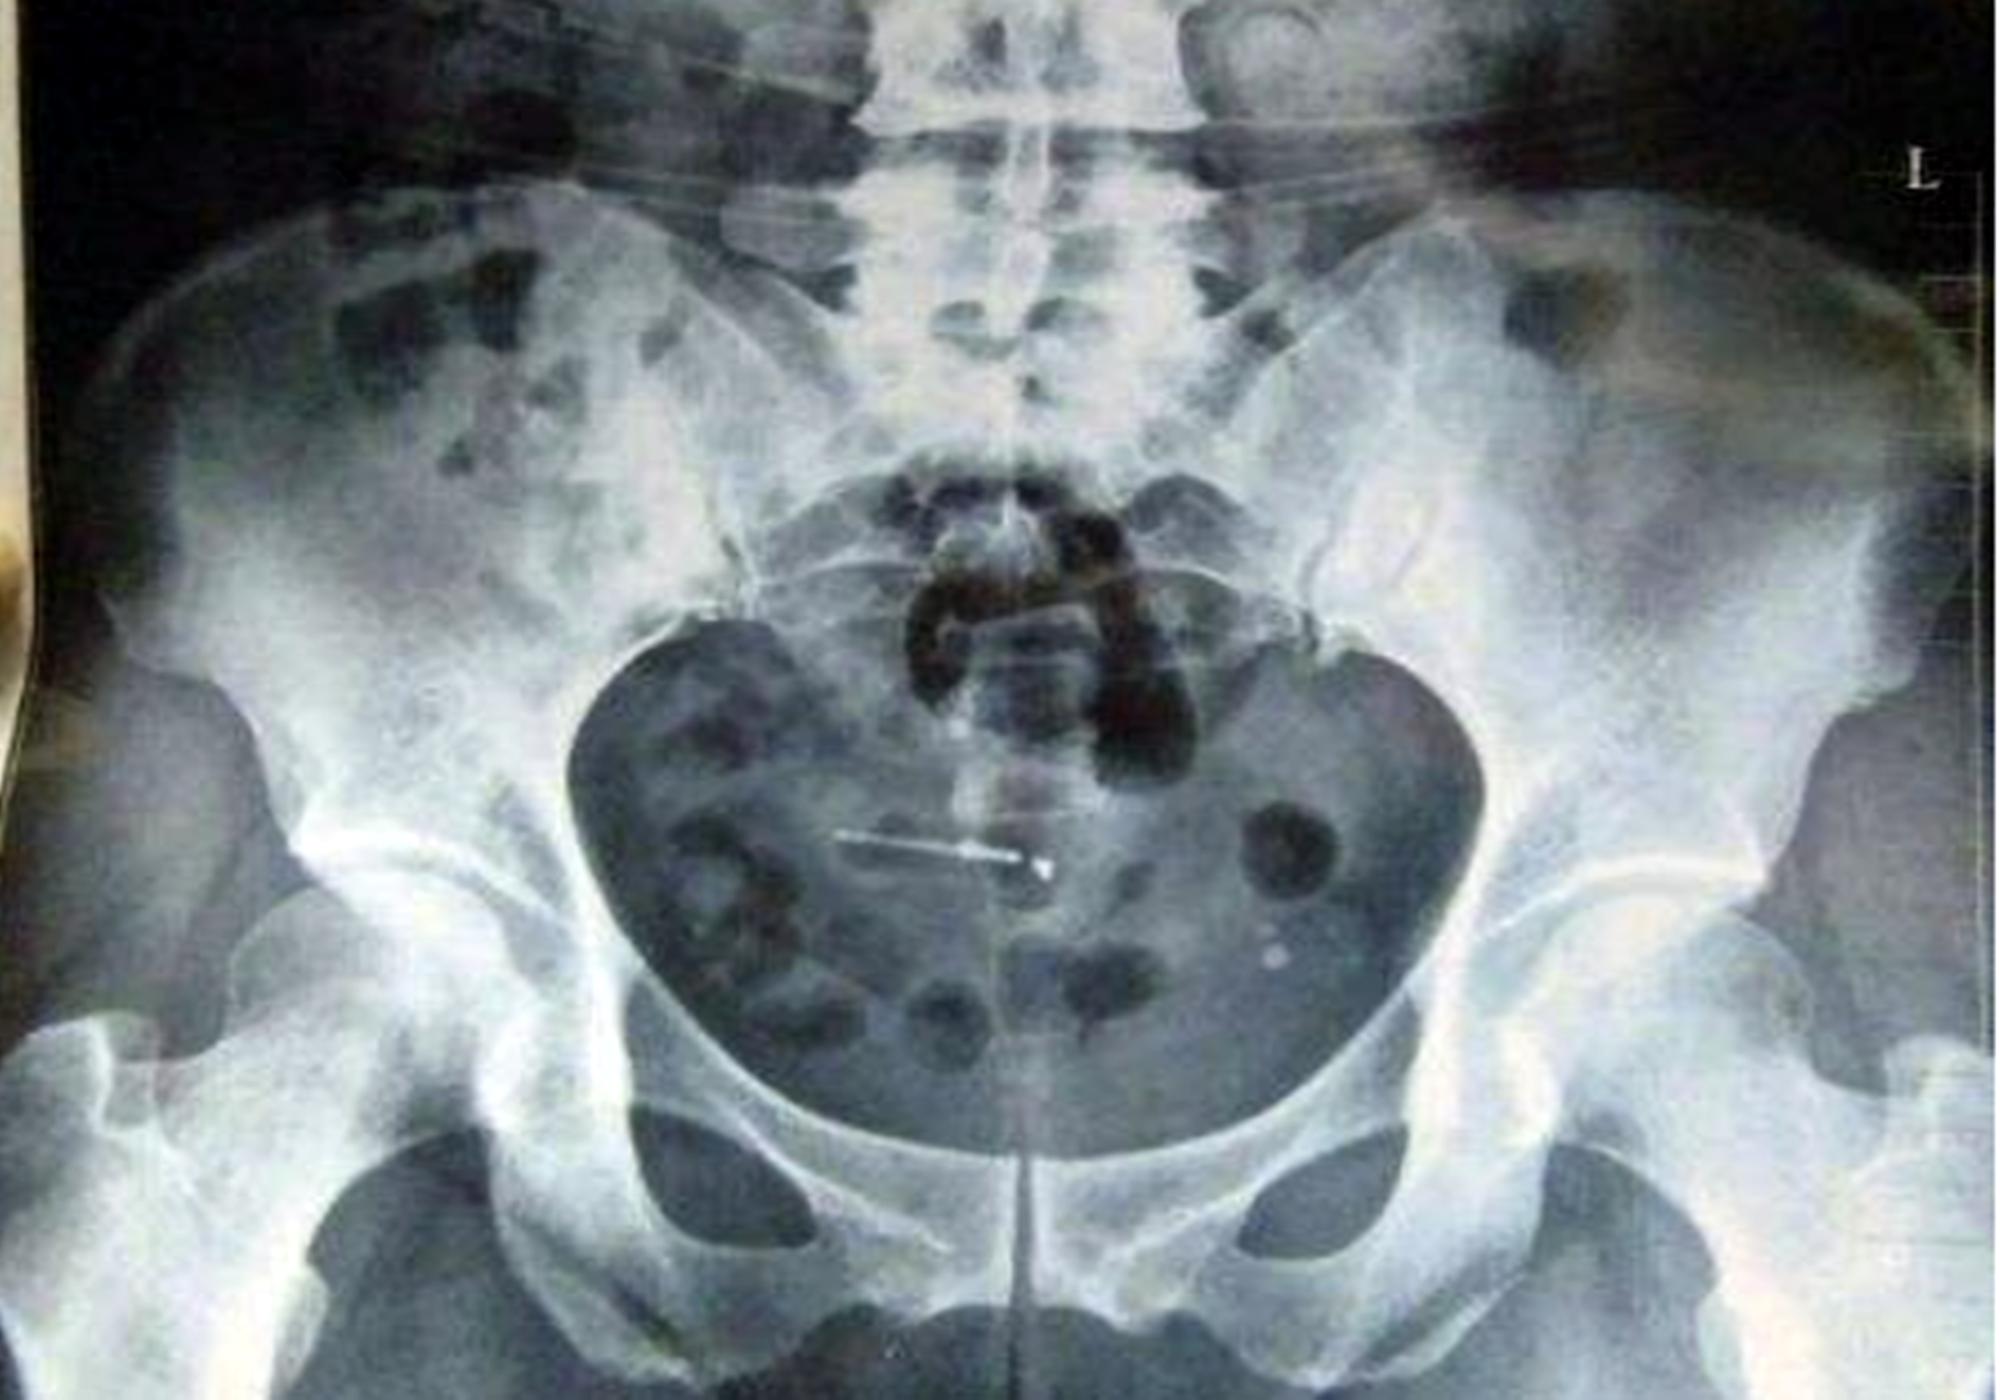

周大姐今年54岁了,前几日因为肚子疼住了医院,这一检查才发现,原来周大姐体内有一个节育环,腹痛是因为节育环竟然从宫内跑进了腹腔,并且扎进了肉里,所以才会疼痛不止。

周大姐细想,这个节育环已经在体内30年了,要不是因为肚子疼,更不不会想到体内还有个这个东西。而且之前一周有腰酸背痛、排便困难的现象,都是因为体内的“节育环异位”所造成的。

医生表示:因为节育环的型号过大,或因在体内放置时间过长,绝经后没有及将节育环取出,都有可能造成这种现象。